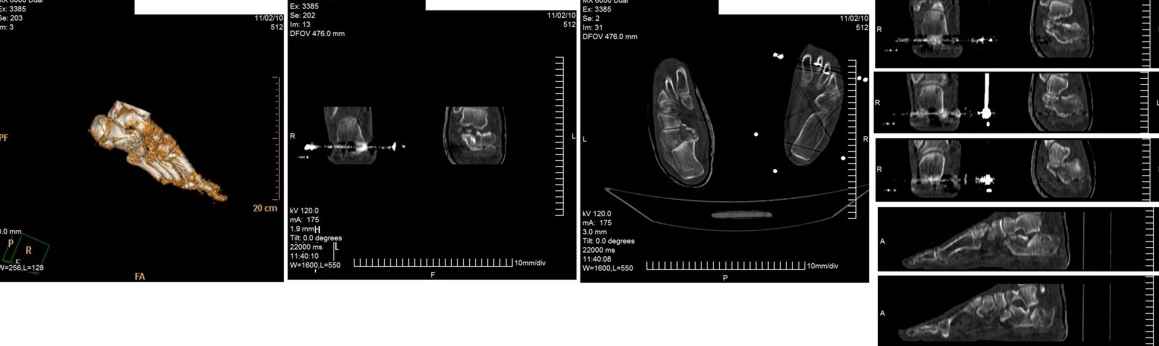

Опираясь на опыт пятидесяти выполненных операций при переломах пяточной кости, мы бы поступили следующим образом.

Безусловно, если есть возможность выполнить КТ подтаранного сустава и пяточной кости до оперативного вмешательства, его необходимо выполнять. Это облегчит планирование оперативного вмешательства. Но для того чтобы решить, что больному в данном конкретном случае необходима открытая репозиция перелома и остеосинтез, достаточно рентгенограммы. Форма пяточной кости сохранена и после репозиции просевшей суставной поверхности пяточной кости угол Белера будет восстановлен. Другим способом, кроме открытой репозиции, поднять просевшую суставную поверхность пяточной кости не представляется возможным. L-образный разрез с латеральной стороны, огибающий латеральную лодыжку. Разрез не должен иметь острых углов (всегда присутствует угроза некроза кожи), сразу доходить да пяточной кости. Отсепаровывать лоскут необходимо сразу от латерального кортикального слоя пяточной кости. В данном случае не следует располагать разрез слишком низко к подошвенной поверхности стопы, так как потребуется только вскрыть подтаранный сустав. Отводятся кверху сухожилия малоберцовых мышц, приподнимается и отводится в сторону сломанная кортикальная пластинка латеральной поверхности тела пяточной кости, поднимается элеватором кверху просевшая суставная поверхность пяточной кости и плотно прижимается к суставной поверхности таранной кости. Проводится две спицы, диаметром 2 мм через пяточный бугор, репонированную суставную поверхность пяточной кости в таранную кость. Скорее всего, потребуется костная пластика образовавшегося дефекта в пяточной кости спонгиозным костным трансплантатом из крыла подвздошной кости. Поскольку у больного повреждены все конечности и вертикализировать его в ближайшие три месяца вряд ли представляется возможным, фиксация двумя спицами будет достаточной. Выполняется интраоперационная рентгенография в двух проекциях. Латеральная кортикальная пластинка тела пяточной кости укладывается на место. Дополнительной её фиксации, как правило, не требуется. Обычно, мы заканчиваем операцию дренированием раны дренажной системой низкого вакуума.

Извините за столь подробное описание. Если необходимо, в понедельник вышлю рентгенограммы похожих случаев.

С моей точки зрения, в данном конкретном случае перелом пяточной кости весьма схож с импрессионными переломами латерального мыщелка большеберцовой кости, когда проваливается только часть суставной поверхности большеберцовой кости, а форма и размеры мыщелка остаются прежними. Поэтому после репозиции нет необходимости в применении массивных имплантантов, большую пользу принесёт костная пластика. В представленном случае длина пяточной кости сохранена, нет типичной варусной деформации отломков на КТ, а спицы нужны лишь для фиксации фрагмента пяточной кости с суставной поверхностью в репонированном положении на суставной поверхности таранной кости. При сращении перелома в таком положении функция подтаранного сустава будет обеспечена, а при сохранённых форме и размерах пяточной кости следует ожидать безболезненной нагрузки.

VlaD.

Операция проведена на 14е сутки после травмы. Фиксация блокируемой пластиной. Трудности - сложность репозиции; необходимость костной пластики (уложен измельченный трансплантат из гребня подвздошной кости 4,5х1,5х1см); множество мелких отломков; большой фрагмент наружной кортикальной пластинки, закрывающий картину в суставе.

followup1.jpg